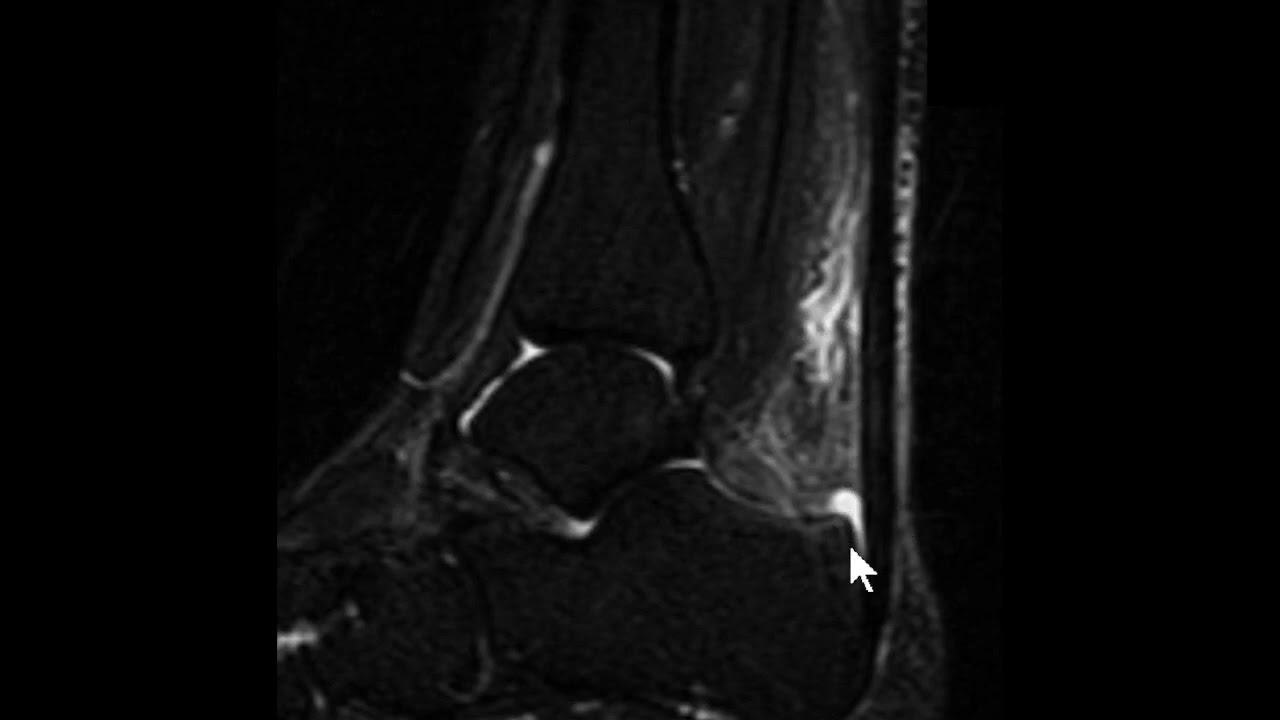

saudações vamos aqui a Mais Um Caso o contexto clínico é de um paciente que sofreu uma torção aguda do tornozelo e temos essa ressonância magnética aqui um axial DP com saturação de gordura e vamos observar aqui aqui é a fíbula corte aqui no plano axial aqui a fíbula aqui o talos aqui a tíbia né então o ligamento tíbio talar anter inferior está íntegro vamos descendo aqui aqui é a topografia do ligamento talofibular anterior aqui o ligamento talofibular posterior e você observa aqui no ligamento talo fibular anterior veja que ele está espessado está com hipersinal e

você nota nitidamente uma solução de continuidade né uma ruptura aí do ligamento talofibular anterior e edema ao seu redor existem outras alterações mas a gente vai se ater a essa alteração o ligamento talofibular posterior ele tem esse aspecto radiado né rajado é normal e o ligamento calcâneo fibular esse aqui na ponta da seta está íntegro apesar de haver edema ao redor dele então o ligamento talo fibular anterior rompeu e essa é a rotura mais frequente ligamentar no tornozelo do ligamento talofibular anterior aqui pra gente ver um comparativo com um tornozelo normal você Observe aqui a

fíbula aqui o talos e aqui você vê o ligamento talo fibular anterior aqui é uma sequência T1 e aqui uma sequência T2 com saturação de gordura você veja aí o ligamento talofibular anterior veja como ele é né em condições normais aí o ligamento talofibular anterior aqui o talo fibular posterior n talo fibular posterior ele tem esse aspecto rajado e descendo um pouco mais o calcâneo fibular fininho aqui subindo calcando fibular saio daqui e vem para cá mas o importante aqui É vermos o ligamento talo fibular anterior normal o aspecto normal dele ok Neste vídeo era